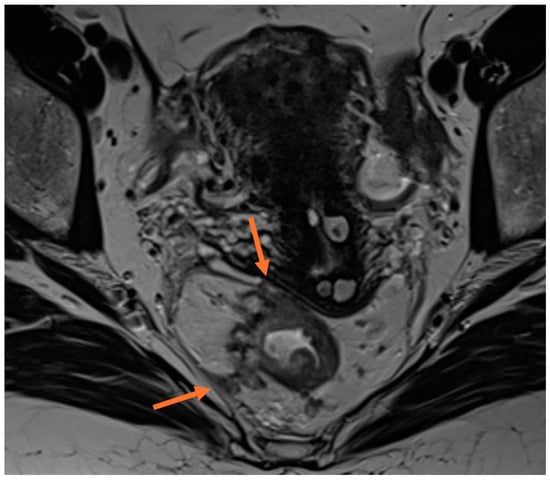

2.5. Lymph Nodes

| Lymph nodes | Malignant lymph nodes criteria: short axis diameter ≥9 mm, 5–8 mm and ≥2 suspicious features, <5 mm and 3 suspicious features, all mucinous lymph nodes; morphologically suspicious features: round shape, irregular border, internal heterogenous signal; |